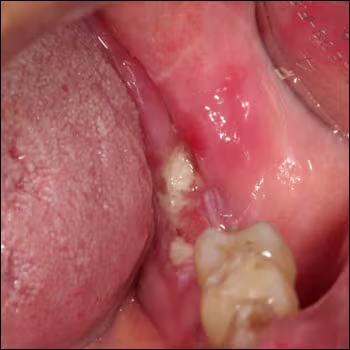

Incidental Keratosis with Ulceration Noted in Patient with Oral Lichen Planus

A 82-year-female presents for a routine check-up and evaluation of her oral lichen planus.